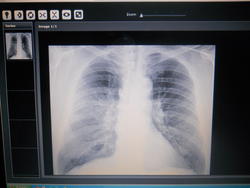

Какая патолотия на снимке?

Иванн,по одному снимку, без анамнеза, жалоб, возраста пациента, трудно определить патологию.Нужен качественный прямой и правый боковой снимки-это минимум.

Пусть будет саркоидоз.

К сожалению других снимков нет возможности выложить--эти два  с промижутком 9. дней--есть ли динамика--была по описанию пневмония--мужчина 63.года--был куртльщик  около 45.лет.

В первом анимке пневмония  в нижней и средней доли правого легкого-во втором пишут что без динамики и под вопросом  про инфильтрат в 3.сегменте---но на 3 раз--снимков  на руках нет-пишут инфильтрат в 2.сегменте.

Потом через 2.5 месяцев--в левом легком не чего не обнаружили.В правом  легочный ри сунок усилен и немного деформирован в прикорневой зоне и 2. сегменте, корень относительно структурный, синусы свободны.

Правый боковой для исключения уплотнения м/д плевры.